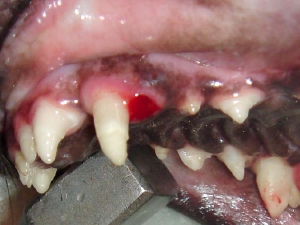

● 歯周病におけるレントゲンの撮影と読影法

中等度の歯周病におかされた歯のデジタルレントゲン撮影

( 無麻酔にて撮影 )

歯周病におかされた歯はほとんど支えている骨がないことに注目します。2番の左側の歯周病は1番の右側をおかしつつあり、2番の右側は3番の左側をおかしつつある。つまり諸悪の根源は、2番の歯であり、2番が1番の右側、3番の左側に影響してしまったという事がこの画像によって明確に理解できます。また赤く表現されている部分は歯石になります。歯の深部まで歯石が付着していることがわかります。当院では、骨残存率50%あれば、まずまずの改善。30%あれば、術後ケアによりより長い歯の寿命。20%以下では、ご家族に抜歯するか、なんとか残すかを伺う。そのような形をとっております。このレントゲン画像であれば、2番は抜歯を推奨し、その部位を縫合することで、1番と3番のこれ以上の歯周病の進行を停止し、1番と3番の寿命を延ばす。5番は歯周病が片側性に深部まで到達しているため、今後、きちんとしたケアができるかどうか? あるいはご家族が抜歯してケアを楽にしたいか、あるは残したいか。という判断にて治療方針を変更する形となります。